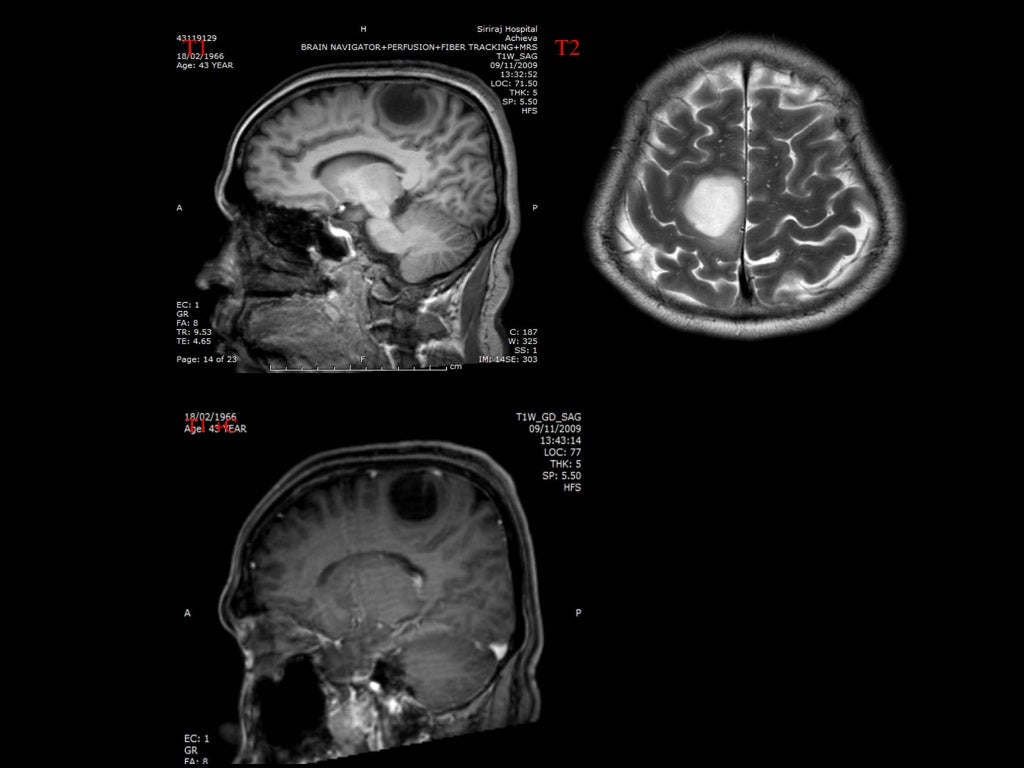

La imagen por resonancia magnética (MRI, MRI) o tomografía computarizada (TC) muestra lesiones en la corteza cerebral. Las lesiones se extienden en todo el espesor de la corteza. En la TC se puede ver densas lesiones de la corteza con discapacidad (hipodensa) bien delimitadas . Los quistes se encuentran a menudo calcificados. Una acumulación de medio de contraste no es típica. Un desplazamiento del tejido circundante no se produce. A veces hay una deformidad del cráneo sobre el tumor. En la RM, las lesiones aparecen bien definidas, no invasoras, y sin edema perifocal (captación de líquido en el parénquima cerebral circundante). Como es típico, la configuración multinodular (que consta de muchos como estructuras nodulares) se ha descrito.[1][7]